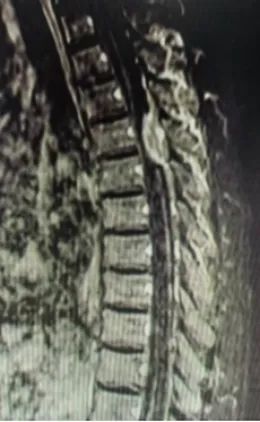

磁共振可以看到肿物位于脊髓后方,椎管狭窄,脊髓严重受压